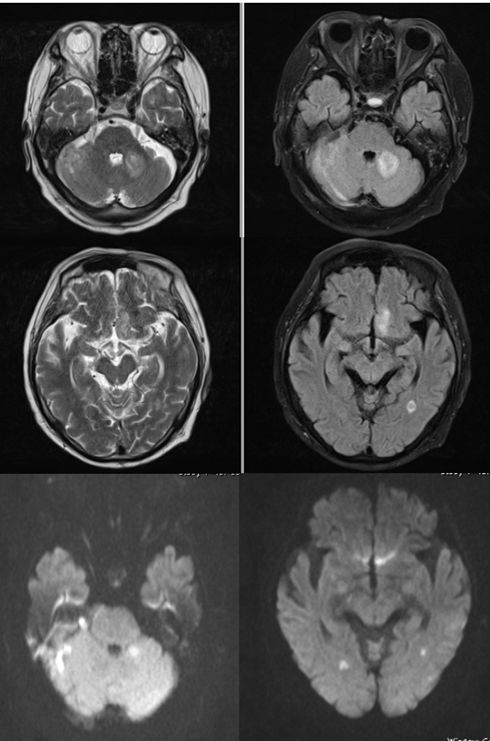

病例4

77岁男性,发热2天,嗜睡1天。查体:嗜睡,呼之能应,不能回答问题,不能按指令完成相应动作,肌力肌张力不能配合。

答案:化脓性脑室炎

补充图片,DWI也证实T2、FLAIR上四脑室、侧脑室似有液平的地方,是积脓。

绿色无坑,充分体现一个临床病例的特点,急性起病,发烧,神经功能缺损。影像上脑室增大,T2、FLAIR上四脑室似有积脓,室管膜高信号。很多人都猜对了。

病例5

74岁男性发热、头痛伴食欲下降1月。

补充病史:既往有皮肌炎,长期服用激素。

答案:脑脓肿

也是发烧,病程稍长。但影像上比较典型,T2、FLAIR高信号的地方,DWI也是高信号,提示脓肿。如果配上增强扫描就更理想了。病史中一是发热,二是有免疫抑制的因素,也提示感染性疾病。